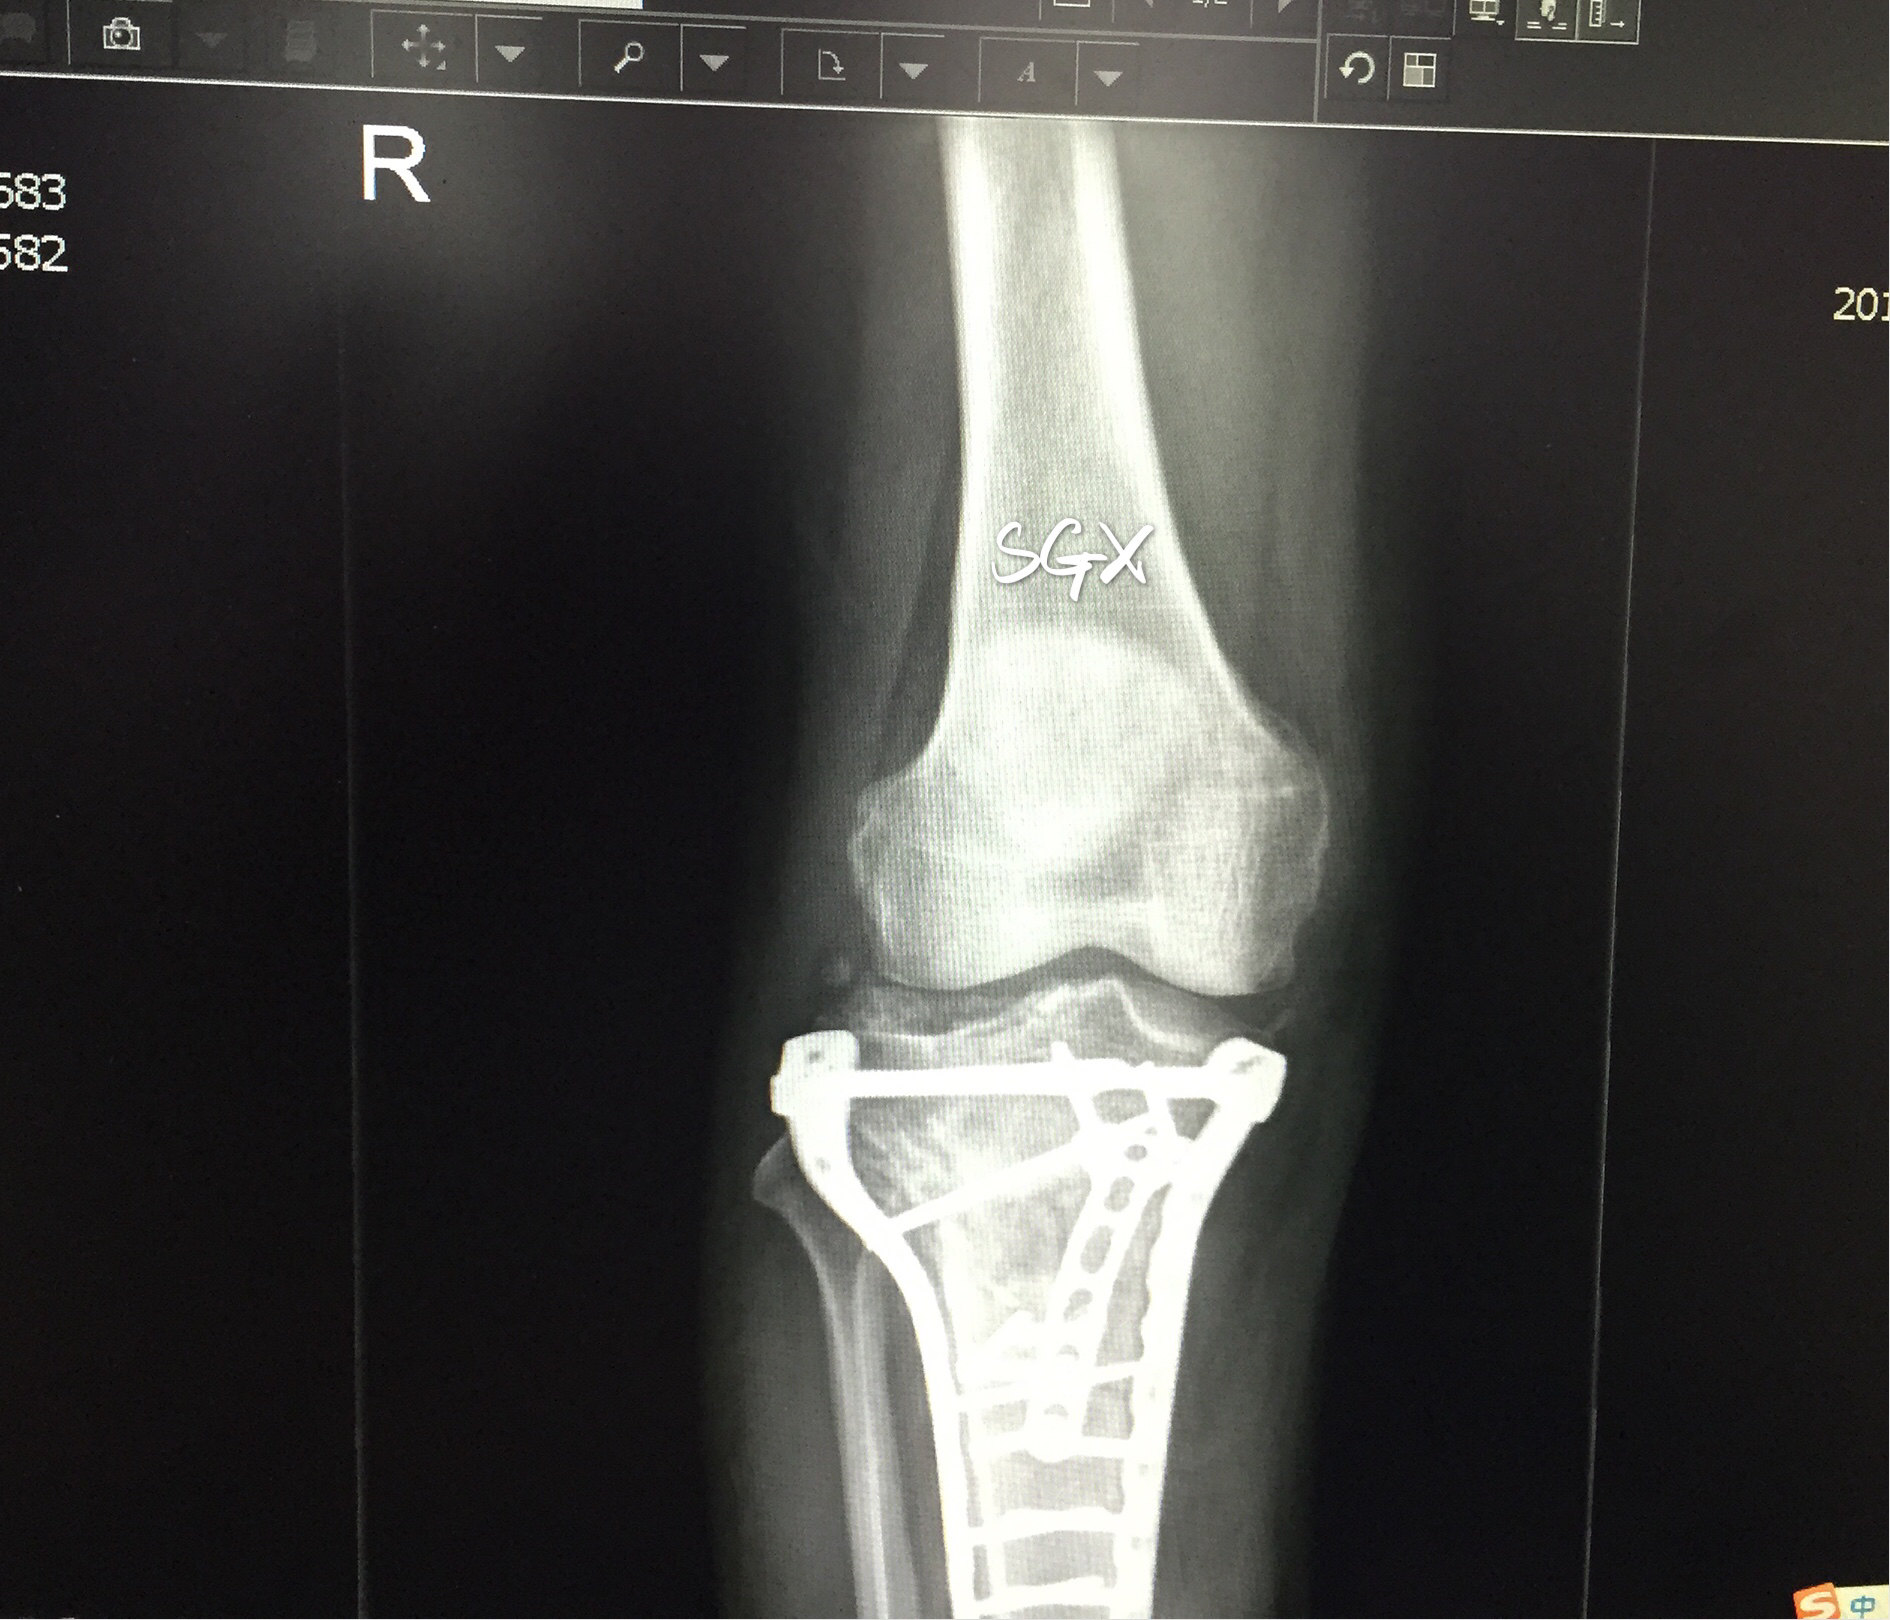

胫骨平台骨折合并股骨远端骨折手术治疗一例 病例中心 诊疗助手 爱爱医医学网

黄骨头胫骨平台骨折手术日记 胫骨平台后外侧粉碎性骨折一例 手术已做 骨科专业讨论版 丁香园论坛

这个平台骨折如何分型及治疗 骨科专业讨论版 丁香园论坛

胫骨平台骨折切开复位钢板螺丝钉固定术 哔哩哔哩 つロ干杯 Bilibili

右胫骨平台及胫骨上段骨折术前 磐安骨伤医院

右胫骨平台及胫骨上段骨折内固定术后 磐安骨伤医院

胫骨平台骨折手术

胫骨平台骨折 知乎